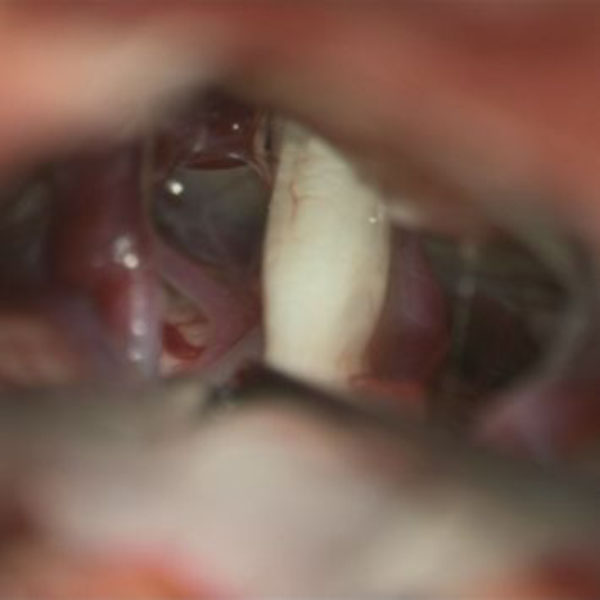

手術中

処置前

処置後